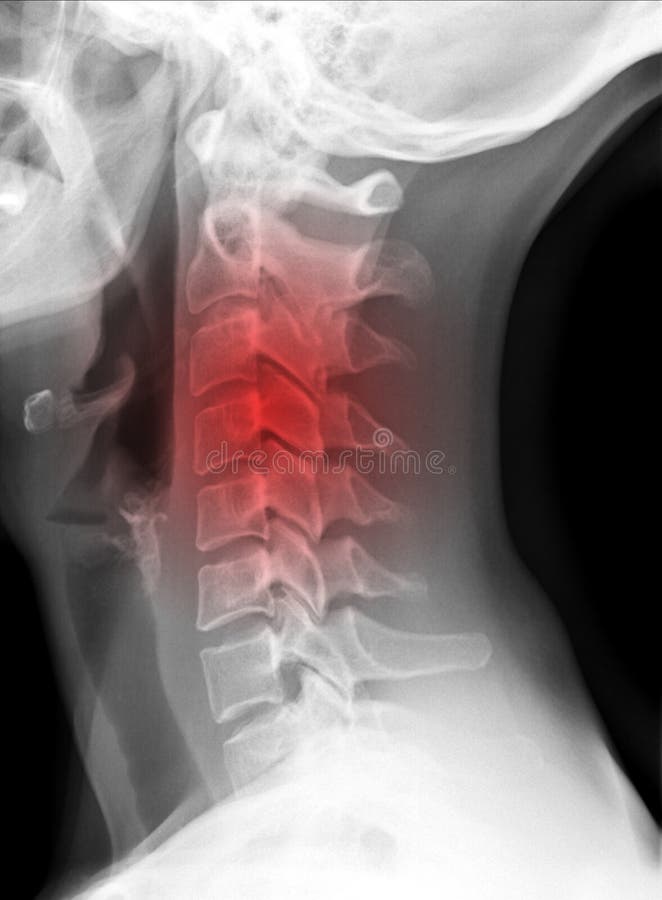

Рентген шеи белое пятно - фото презентация